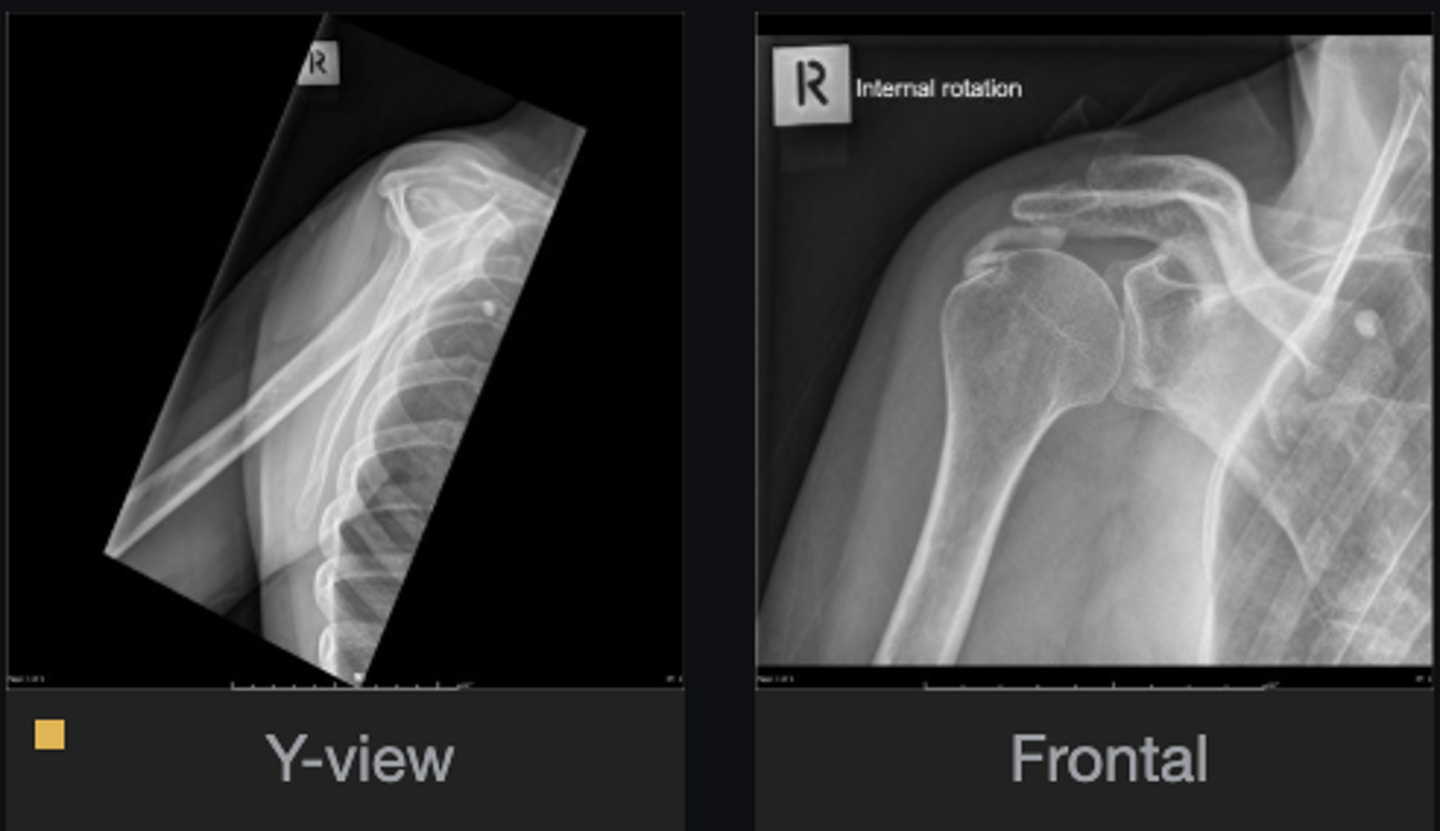

- Calcification of supraspinatus tendon

- Acromiohumeral interval enlarged

List the abnormal findings

Hydroxyapatite Deposition Disease

Diagnosis?

Supraspinatus

What tendon is involved?

Calcification in lung

Do you see anything else that is abnormal?

- Increased acriohumeral interval

- Glenohumeral subluxation

- Globular calcification in acromiohumeral interval